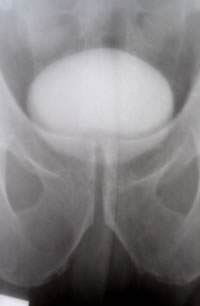

ОБСЛЕДОВАНИЕ

Рентгенологическое исследование

нижних мочевых путей (НМП)

Цистотонометрия-

детрузорная гиперактивность.